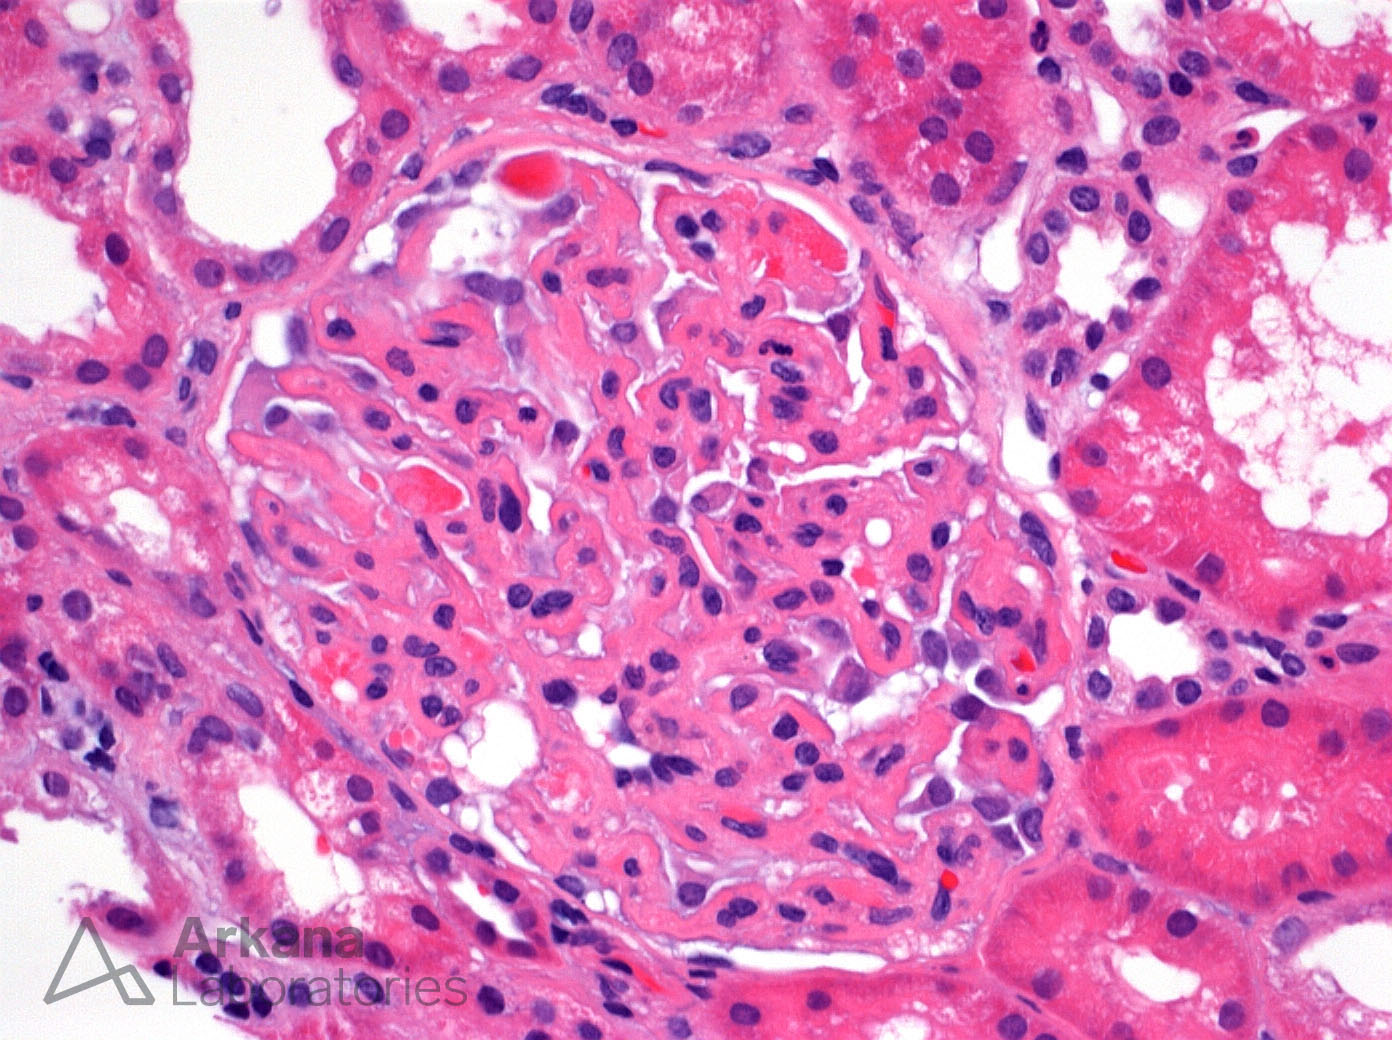

Previous Image Next Image Glomerular Fibrin Thrombi in a Patient with Preeclampsia on H&E Like Loading...